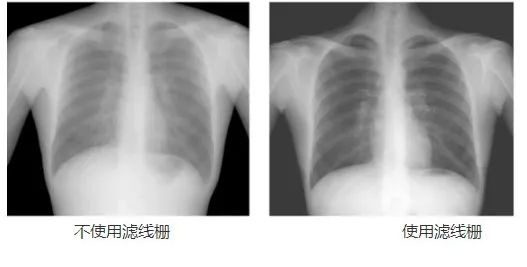

動態(tài)DR工作中的常用部件——濾線柵,可以幫助過濾散射線,降低灰霧度,提高對比度,從而提高成像質(zhì)量